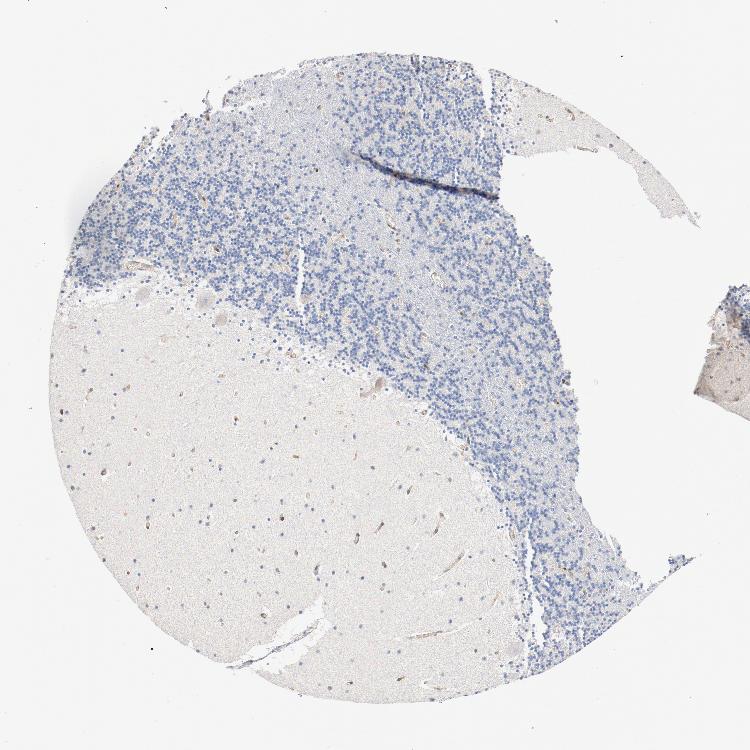

CEREBELLUM - Antibody stainingi

Antibody staining in the annotated cell types in the current human tissue is reported as not detected, low, medium, or high, based on conventional immunohistochemistry profiling in selected tissues. This score is based on the combination of the staining intensity and fraction of stained cells.

Each image is clickable and will lead to virtual microscopy that enables deeper exploration of all samples and also displays staining intensity scores, fraction scores and subcellular localization as well as patient and tissue information for each sample.

Antibody CAB004041

Purkinje cells Not detected

Cells in granular layer Not detected

Cells in molecular layer Not detected